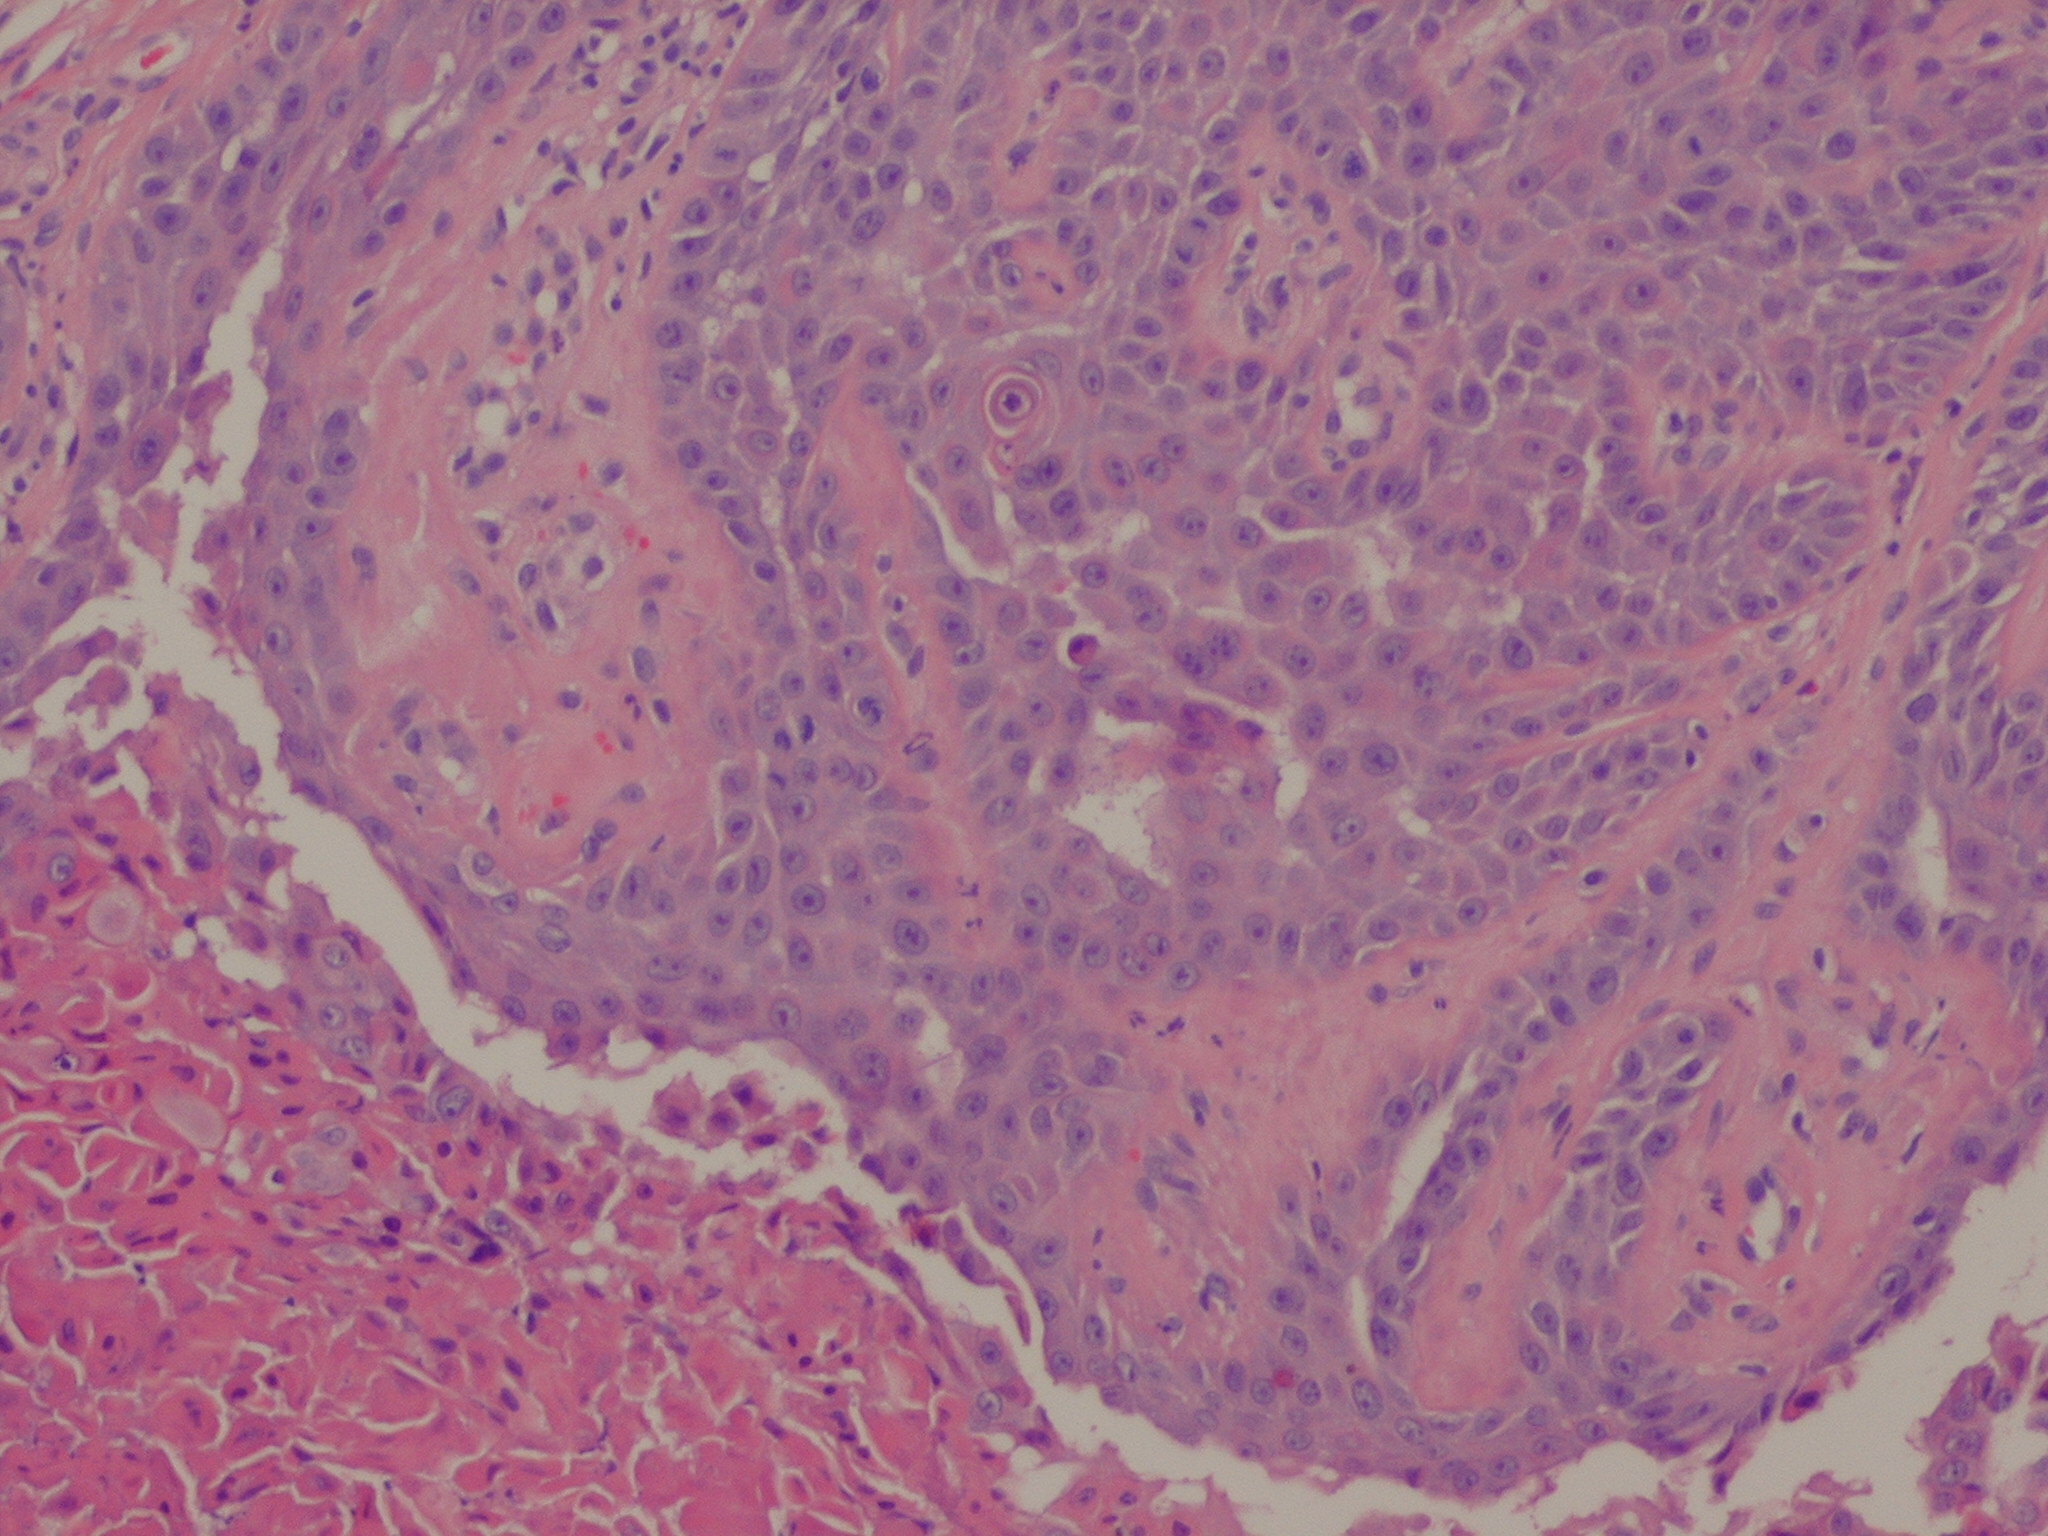

The center of the lesion is occupied by a large, cup-shaped invagination connected with the surface by a channel filled with keratinous material . The large invagination contains numerous acantholytic, dyskeratotic cells in its upper portion. The lower portion of the invagination is occupied by numerous villi, that is, markedly elongated dermal papillae that are often lined with only a single layer of basal cells and project upward from the base of the cup-shaped invagination  . Typical corps ronds can I

usually be seen in the thickened granular layer lining the channel at the entrance to the invagination .